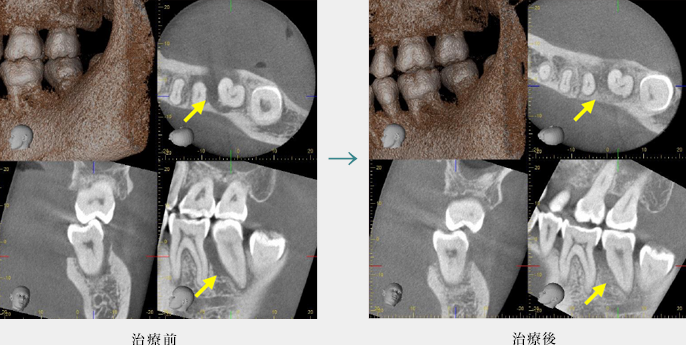

再生療法

歯周病の進行によって溶けてしまった骨を、歯周再生療法によって回復しています。

こちらはCTによる3次元的な画像です。

歯周病による骨の溶け具合は、歯の形態や位置によって様々です。

歯の裏側だけに限局していることもあれば、歯の全周で進行することもあります。

歯周病の診断には、3次元的に骨の形態が把握できるCT撮影が有効です。

CT画像から、歯周病の病態・進行程度を診断し、治療計画を立案します。

(ただし、再生療法は骨の溶け方によっては適応が困難な場合もあります。)